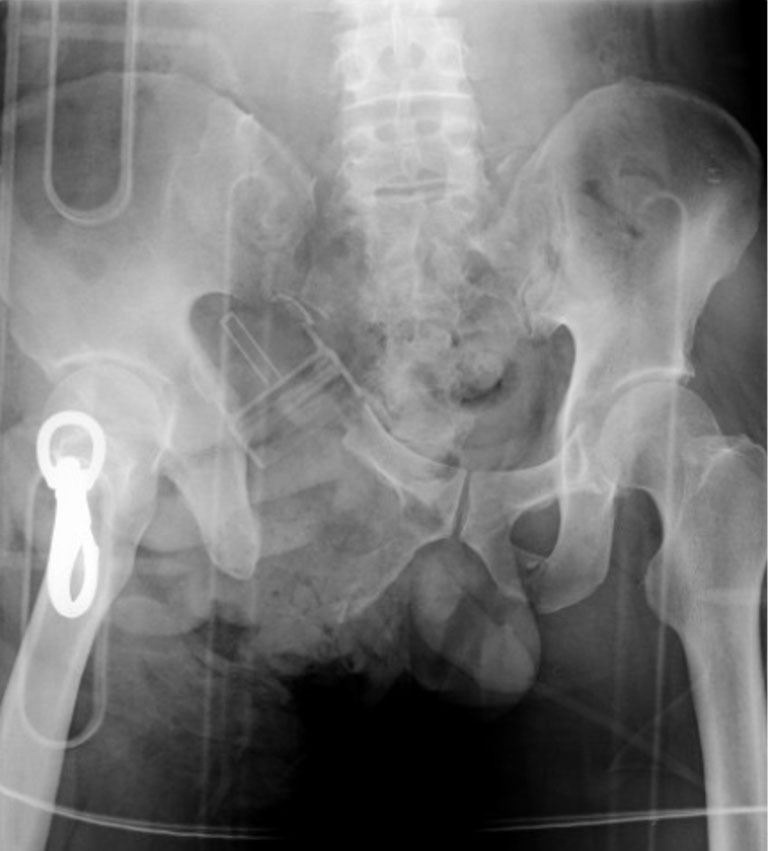

Case description: A healthy 41-year-old man presented with an open pelvic ring fracture and a laceration in the lower abdomen sustained at an ironworks. His hemodynamic status was unstable. Pelvic ring stabilization with an external fixator, ligation of the median sacral and bilateral internal iliac arteries, partial resection of the ileum, appendectomy, and intra-abdominal pelvic packing were performed. Seven days after the injury, he developed a single spike fever of 39.8 ℃ with a significant pus discharge from the open wound around his groin. A computed tomography scan revealed an accumulation of gas around the sacroiliac joint, in the abdominal cavity, and the adductors and gluteus maximus muscles caused by non-clostridial gas gangrene. We performed surgical debridement three times and initiated vancomycin administration. Hyperbaric oxygen therapy was also initiated as an adjunctive therapy. The patient could walk with a cane 5 months after the injury.